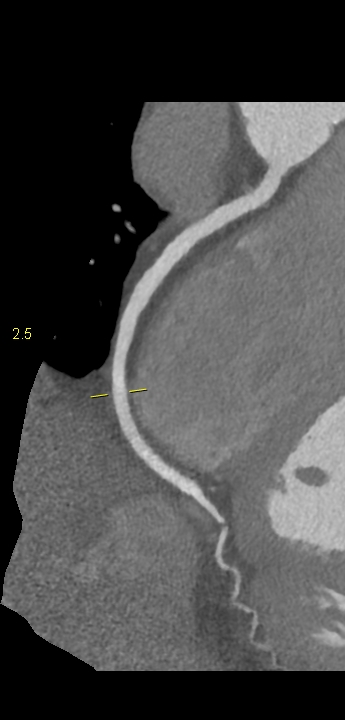

Figururile 1-9: reconstrucție în axul lung al vasului pentru arterele coronare cu evidențierea unui calibru global crescut la nivelul acestora și cu încărcătură ușoară-moderată de placă în principal calcificată

Discuţie caz nr 132: Examinările coroCT se efectuează în principal pentru aprecierea încărcăturii de placă precum și pentru evidențierea reducerilor de lumen ce necesită tratament. Această examinare a evidențiat creștere globală a calibrului arterelor coronare și o încărcătură ușoară-moderată cu placă în principal calcificată, fără a se evidenția arii de stenoză.

DE LUAT ACASĂ!!! Ectazia coronariană este o afecțiune rară caracterizată prin dilatarea anormală (diametrul vasului este de 1.5 ori mai mare) a arterelor coronare, care poate duce la afectarea fluxului sanguin și la un risc crescut de ischemie. Etiologia nu este cunoscută iar afecțiunea poate fi asociată cu ateroscleroză sau factori congenitali și reprezintă o provocare atât în diagnostic, cât și în tratament. Simptomele se suprapun adesea cu cele ale altor boli coronariene, ceea ce face ca identificarea timpurie să fie crucială. Opțiunile de tratament variază de la tratamentul medical cu terapie antiplachetară sau anticoagulantă până la proceduri intervenționale, cum ar fi angioplastia sau intervenția chirurgicală, în funcție de severitatea și riscul de complicații. Tratamentul pe termen lung se concentrează pe prevenirea evenimentelor ischemice și pe abordarea cauzelor care stau la baza acestora.